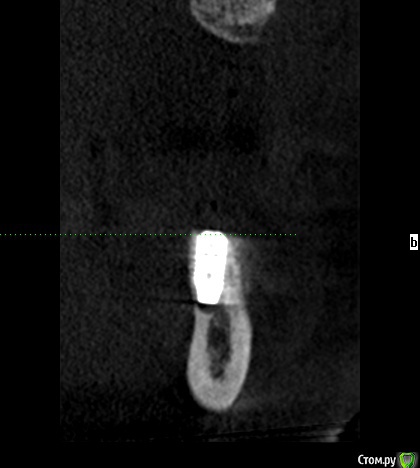

igorgergg Опубликовано 25 апреля, 2018 Поделиться Опубликовано 25 апреля, 2018 Всем привет, нужно экспертное мнение) Хочется сразу поставить имплпнты вместе с НКР. Прикладываю снимки КТ. По высоте все гуд, зафиксироваться проблемы не будет. Вопрос в том что половина импланта в правильном положении будет оголена. Естественно возле импланта уложу ауто стружку со скребка, а остальное забиваю церабоном с ауто 50/50. Нужен взгляд со стороны, спасибо. Ссылка на комментарий